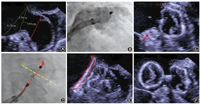

所有患者术前均行TEE、TTE检查,以除外左心房血栓,并测量左心耳数据、评估心功能和瓣膜情况。左心耳开口,定义解剖学开口[15],即左上肺静脉(left superior pulmonary vein,LSPV)嵴部与左回旋支(left circumflex,LCx)处连线(图1)。但2类封堵器测量稍有差别。使用PLO所测量的左心耳开口,位于连线内侧,等同于封堵器展开后最大直径平面所在位置的径线,而DLO所测量的为连线外口。左心耳深度,为开口线中点垂直线至内壁最深的径线。DLO需要测量封堵盘的锚定区(landing zone)直径,为平行开口线以内5~10 mm处的径线[6,15]。建议还需要参考LSPV嵴部至二尖瓣瓣环根部的距离,此为封堵盘最大直径。

我中心使用的左心耳封堵器,包括6种不同品牌(图2)。分别为Watchman封堵器[3]、LAmbre封堵器[10]、Lefort封堵器[12]、Leftear封堵器、Lacbes封堵器和ACP封堵器[4,13]。依据封堵器的固有形态和植入流程,归类为两大类:"塞式"封堵器(plug-like occluder,PLO )和"盘式"封堵器(disc-like occluder, DLO)。PLO包括Watchman封堵器及Lefort封堵器2种,均有21、24、27、30及33 mm 5种规格。DLO包括LAmbre封堵器、ACP封堵器、Lacbes封堵器及Leftear封堵器4种。两种封堵器均包含固定盘(伞)和封堵盘,固定盘的大小在15~36 mm,封堵盘比固定盘大4~6 mm。相比于PLO,DLO可覆盖更大或更小规格的左心耳。而LAmbre封堵器和Leftear封堵器有一类"小伞大盘"的特殊型号,封堵盘比固定盘大12~14 mm[6],为封堵特殊形态的左心耳带来了另一种可选的植入方式。

注:"塞式"封堵器包括Watchman封堵器及Lefort封堵器2种,"盘式"封堵器包括ACP封堵器、LAmbre封堵器、Lacbes封堵器及Leftear封堵器4种

5.评估"PASS"原则(图4):Position(位置),器械最大直径平面正好或者稍远于并横跨左心耳开口;Anchor(锚定):通过牵拉确认封堵器固定好;Size(封堵器选型):封堵器实际展开最宽径相对于所选型号,应有一定的压缩;Sealing(封闭):保证所有的瓣叶都在器械远端并封闭,TEE测定封堵器残余分流≤ 5 mm[3,16]。

6.满足原则则释放封堵器。若不满足,则再回收以后重新定位释放,直至成功。(1) LAmbre封堵器评估"COST"原则:LCx:固定盘在LCx后面展开;Open(展开):固定盘充分展开,末端与连接在密封盘和固定盘之间的显影标志在一条直线上;Sealing(封闭):密封盘达到最佳封堵,TEE测定残余分流(peri-device leak, PDL) ≤ 3 mm[3,16];Tug test(牵拉):通过牵拉确认封堵器固定好(图5)。(2)ACP和Lacbes评估"CLOSE"原则:LCx:固定小叶展开后至少2/3要在LCx后面;Lobe(固定小叶):固定小叶要有一定压缩;Orientation(轴向):固定盘要与封堵器径线垂直;Separation(分离):固定盘和封堵盘要分离;Elliptical(椭圆形):封堵盘要有一定的形变(图6)。(3)Leftear评估"CODIS"原则:固定盘在LCx后面展开;固定盘充分展开(Open );封堵盘(Dish)要有一定的形变;通过牵拉确保固定牢靠(Insurance);密封盘达到最佳封堵(Sealing),TEE测定PDL ≤ 3 mm。